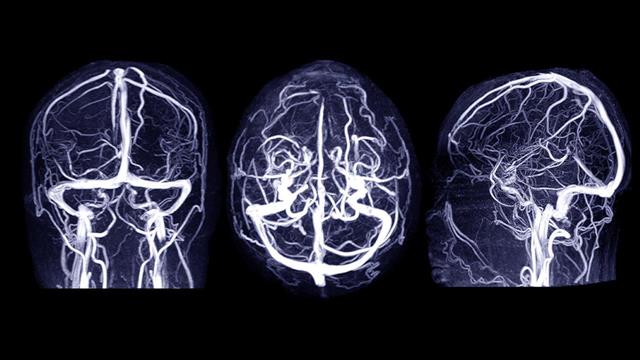

Συνήθη φάρμακα για τον έλεγχο της υψηλής χοληστερόλης του αυξημένου σακχάρου και της υπέρτασης θα μπορούσαν επίσης ενδεχομένως να μειώνουν τον κίνδυνο ενός ανθρώπου για εγκεφαλική αιμορραγία, αναφέρει νέα έρευνα.

Οι ερευνητές αξιολόγησαν τον κίνδυνο ανευρύσματος στον εγκέφαλο που προκαλεί αιμορραγικό εγκεφαλικό επεισόδιο.